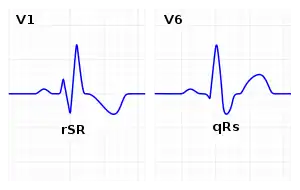

| ECG characteristics of a typical RBBB showing wide QRS complexes with a terminal R wave in lead V1 and a prolonged S wave in lead V6. | |

Diagnosis requires that the QRS complex is greater than 120 ms and an rsR' wave is present in lead V1 or V2.[2] The T waves are generally flipped in V1 and V2.[2] When the QRS duration is less than 120 ms, but the other criteria are present, it is called an incomplete RBBB.[1] Its presence does not interfere with the diagnosis of a heart attack.[1]

The criteria to diagnose a right bundle branch block on the electrocardiogram:

- There should be a terminal R wave in lead V1 (often called "R prime," and denoted by R, rR', rsR', rSR', or qR).

- There must be a prolonged S wave in leads I and V6 (sometimes referred to as a "slurred" S wave).